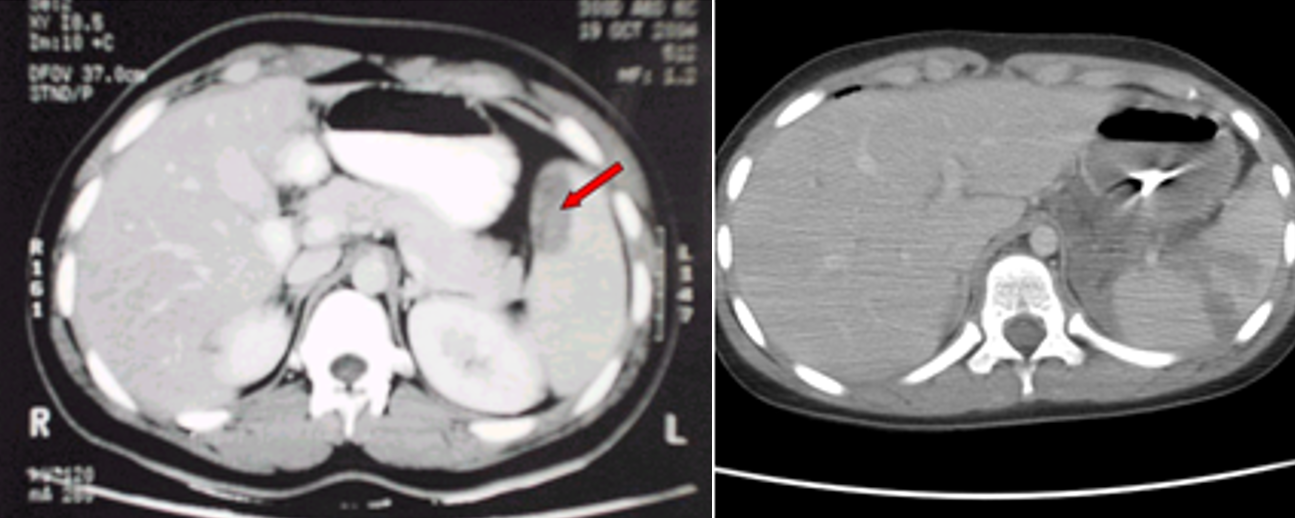

(Image: Splenic injury (CT scan))

• Diagnosis: - Z - CT in hemodynamically -stable patients

- FAST or exploratory laparotomy in an unstable patients